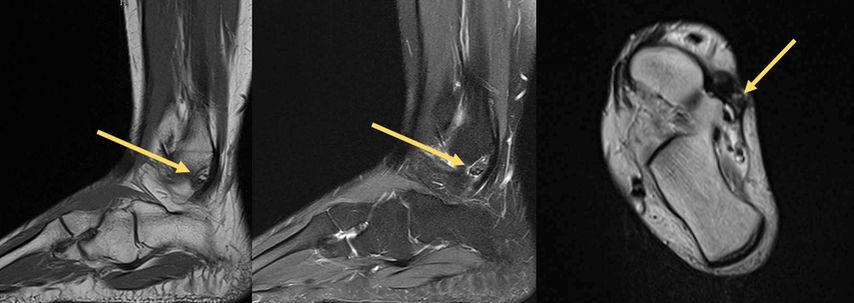

Der tenosynoviale Riesenzelltumor (TSRZT), welcher im deutschsprachigen Raum früher als PVNS (pigmentierte villonoduläre Synovitis) bezeichnet wurde, stellt wohl mit ca. 1,8 Neuerkrankungen pro 100000 Einwohnern pro Jahr die größte Gruppe an Läsionen dieser Art am Bewegungsapparat dar. Der Nomenklatur der WHO folgend soll der Terminus PVNS nicht mehr verwendet werden, da es sich histologisch um dieselbe Entität wie TSRZT handelt.6–9 Der TSRZT der Weichteile darf nicht mit dem des Knochens verwechselt werden. Der TSRZT kann ursächlich für synoviale Verdickungen und ein Überwachsen sein, wie in Abbildung 1 dargestellt. Normalerweise produziert die Synovia eine kleine Menge einer viskösen Flüssigkeit, welche die Gelenke bzw. den Knorpel „schmiert“ und so zu einem physiologischen Bewegungsablauf beiträgt. Der TSRZT produziert vermehrt diese Flüssigkeit, was Schwellung und Schmerz nach sich zieht. Oftmals wird dieser Zustand mit Erkrankungen aus dem rheumatoiden Formenkreis verwechselt. Im Falle des Vorliegens eines TSRZT ist die Dunkelziffer groß.8 Diese gutartigen Tumoren entstehen aus synovialem Gewebe: Gelenken, Sehnenscheiden oder Bursen. Große Unterschiede gibt es im lokalen Verhalten, man unterscheidet eine lokal aggressive (diffuse) von einer nodulären Wachstumsform (Abb. 2). Eine Metastasierung oder eine sarkomatöse Transformation sind extrem selten. Die diffuse Form wird von vielen als schwieriger in der Behandlung wahrgenommen, da sie destruktiver wächst und eine höhere Rezidivrate hat.10–12

Abb. 1: MRT eines tenosynovialen Riesenzelltumors (TSRZT) des Musculus tibialis posterior